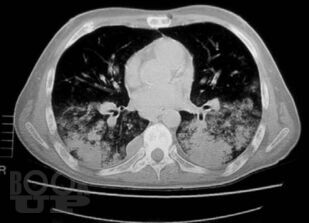

Книга профессора П.В. Власова посвящена современному состоянию лучевой диагностики заболеваний органов грудной полости. Она является первой в отечественной литературе крупной работой, в которой освещена диагностика заболеваний органов грудной полости: острых пневмоний и плеврита, хронических неспецифических заболеваний легких, туберкулеза органов дыхания, рака легкого, опухолей плевры, диффузных и диссеминированных процессов легких, опухолей и кист средостения. Все вопросы рассматриваются с учетом самых современных взглядов на патогенез и диагностику заболеваний.

Большим достоинством книги является комплексный подход к диагностике заболеваний. Наряду с традиционными методами ретгенологического исследования, такими как рентгенография и линейная томография, в книге получили полное освещение роль и место в современном комплексе диагностических средств такие методы, как компьютерная томография и ультрасонография, значительно расширившие возможности диагностики заболеваний.